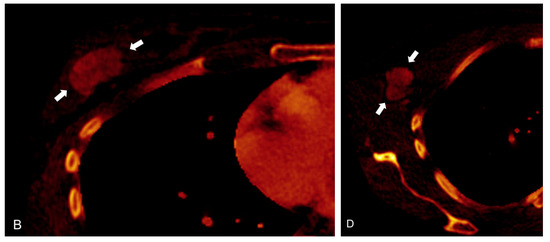

- Zhang, X.; Zheng, C.; Yang, Z.; Cheng, Z.; Deng, H.; Chen, M.; Duan, X.; Mao, J.; Shen, J. Axillary Sentinel Lymph Nodes in Breast Cancer: Quantitative Evaluation at Dual-Energy CT. Radiology 2018, 289, 337–346. [Google Scholar] [CrossRef]

- Zhou, Y.; Su, G.Y.; Hu, H.; Ge, Y.Q.; Si, Y.; Shen, M.P.; Xu, X.Q.; Wu, F.Y. Radiomics analysis of dual-energy CT-derived iodine maps for diagnosing metastatic cervical lymph nodes in patients with papillary thyroid cancer. Eur. Radiol. 2020, 30, 6251–6262. [Google Scholar] [CrossRef] [PubMed]

- Choe, J.; Lee, S.M.; Do, K.H.; Lee, J.B.; Lee, S.M.; Lee, J.G.; Seo, J.B. Prognostic value of radiomic analysis of iodine overlay maps from dual-energy computed tomography in patients with resectable lung cancer. Eur. Radiol. 2019, 29, 915–923. [Google Scholar] [CrossRef] [PubMed]